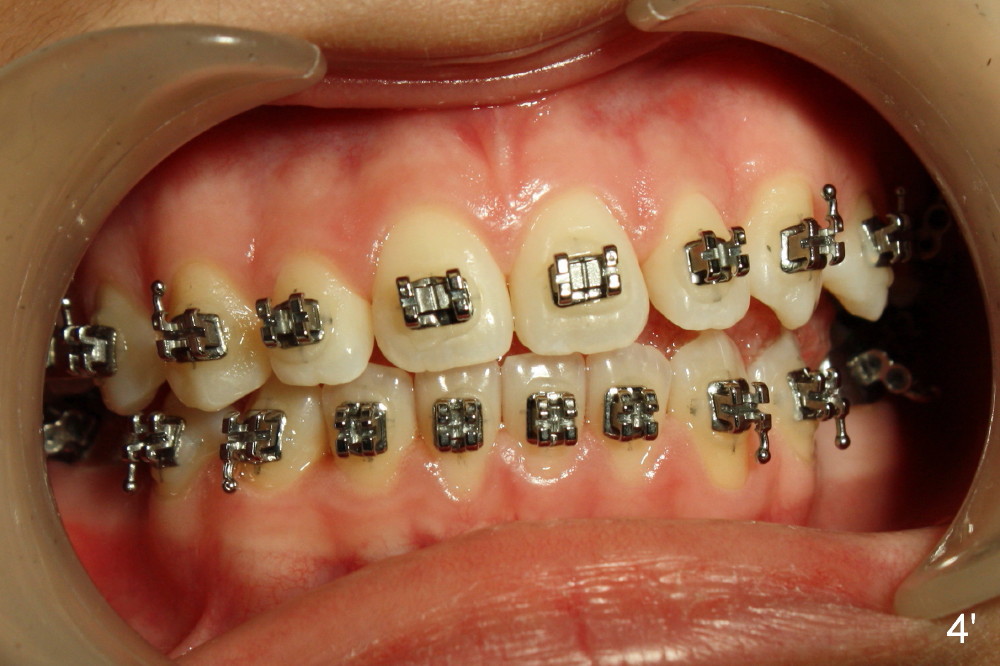

A 13-year-old Asian girl seeks orthodontic treatment for crowding. The lower 2nd bicuspids are congenitally missing (Fig.1,8), whereas the upper right one rotates 180° and the upper left is partially impacted (Fig. 1, 7). The lip muscles strain when the lips close (Fig.3). Orthodontic treatment started with extraction of four affected teeth (#4,13, K and T) 6 months ago. .018' niti wires are being used. Dental midlines do not coincide preop and intraop (Fig.4,4'). Pre-op front view shows that the upper dental midline coincides with the facial one (Fig.1'). There is Class I canine and molar relationship on the right (Fig.5,5',9,9'); open bite on the left (Fig.6,6',10,10').

Update: The left open bite was closed less than one month by wearing elastics between upper and lower teeth (Fig. 6'''). The occlusal plane and midline improve (Fig.4''). Wires have gradually changed to .016x.016, .016x.022 and now .018x.025 with power chains. All the spaces are closed except the one in LR (Fig.7''-10''). What I cannot accomplish is to fix meisal (Fig.5'' (white line), 9'') and lingual (Fig.8'' arrows) inclination of LR molars, although elastic is instructed to be placed between UR7 buccal and LR7 lingual. The rectangular wires could be twisted to fix lingual inclination. Which should be done first: LR space or LR molar inclination? Click each figure for magnification.